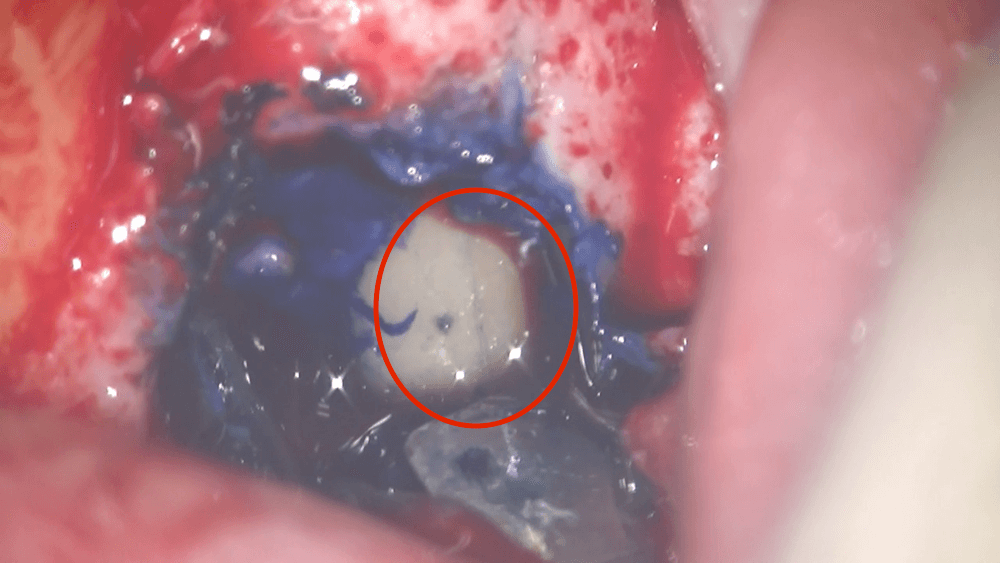

根の表面をマイクロスコープで確認すると、ヒビが入っていました。

⭕️で囲みました。このような場合は、基本的に抜歯なります。歯茎の腫れの原因は、根の表面に入ったヒビに入り込んだ汚れであり、その汚れを、抜歯という外科的処置にて取り除く、ということになります。

患者さんは、なぜ抜歯なのか?ということを知りたいはずです。当院では、このように、マイクロスコープを用いて、動画で説明し、患者さんに納得していただく治療を心がけています。歯科の治療の本当に価値は、患者さんの目の見えないところにあります。これを、患者さんに見てもらうには、マイクロスコープで撮影した動画が必須です。